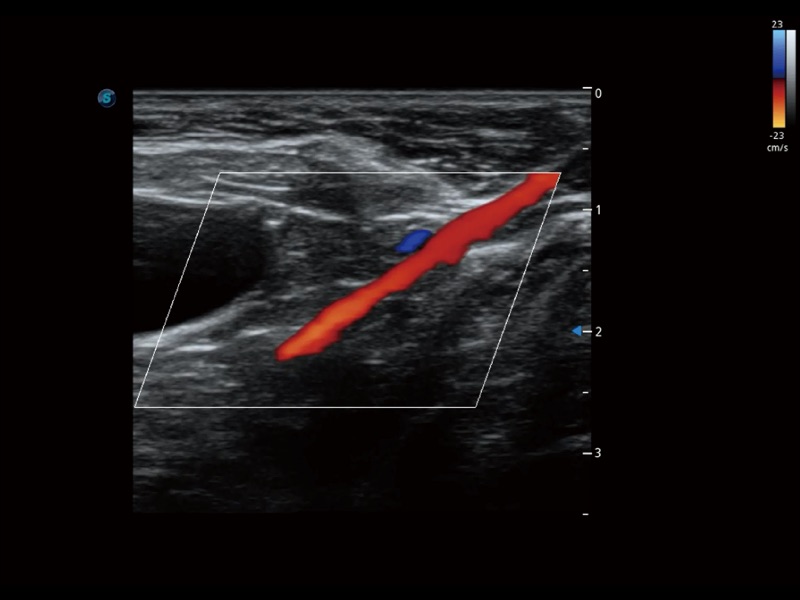

优异的基础图像

(犬)髂动脉血流